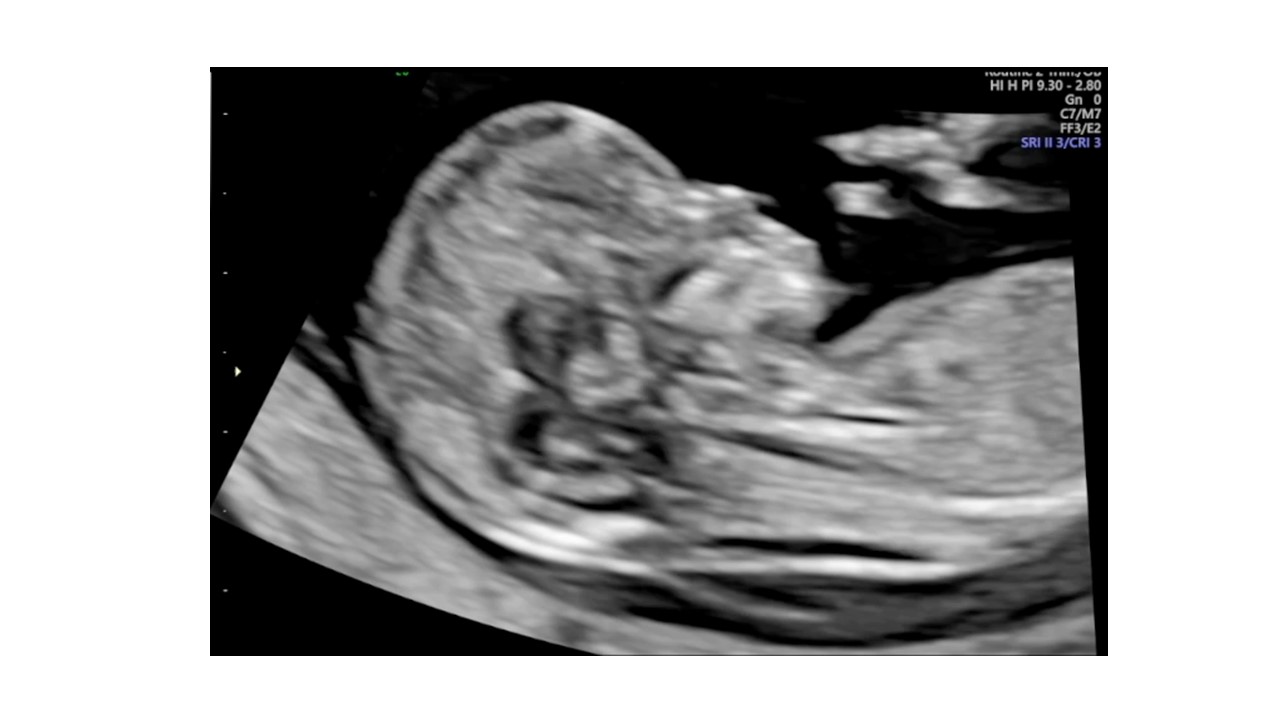

Siêu âm hình thai học quý I

ThS. BS CKII Nguyễn Đình Vũ - Khoa CĐHA, Bệnh viện Hùng Vương